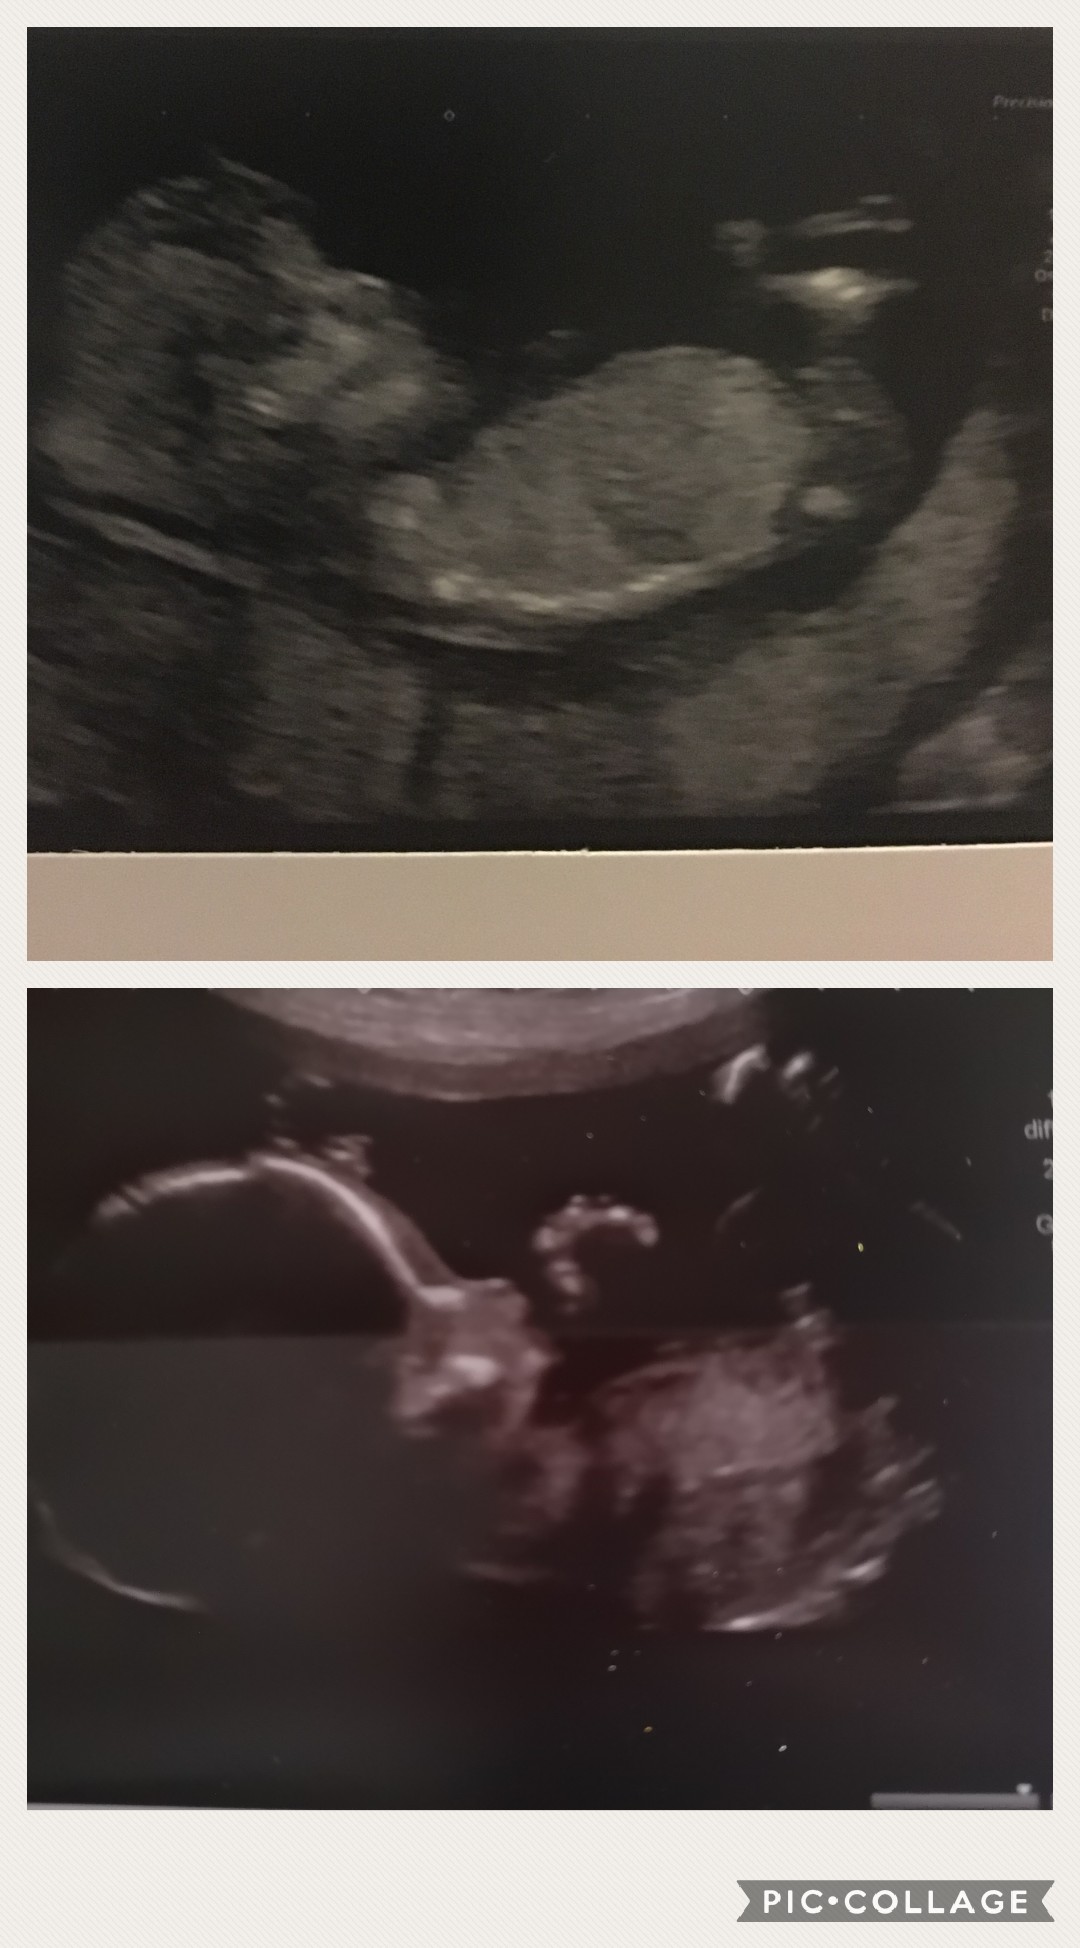

Do you think Girl or Boy? 15 days till due date so a bit if fun to keep me going!! First scan is 12 weeks, second is from 20 weeks. Thankyou Attachment 40162

Maybe boy from the 12 week pic. The nub looks stacked if that's what I'm seeing but it's hard to tell. The 20 week pic we need a potty shot.